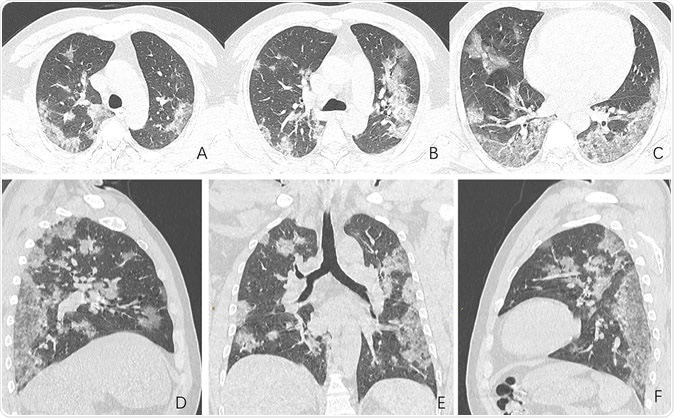

Images in a 44-year-old man who presented with fever and suspected COVID-19 pneumonia. A-C, Thin-slice (1-mm) axial CT images showed multiple patchy ground-glass opacity along the peribronchial and subpleural lungs. Some reticular opacities were also found within areas of ground glass (crazy-paving pattern). Lymphadenopathy was absent. D-F, Multiplanar reconstruction showed diffuse distribution of lesions.